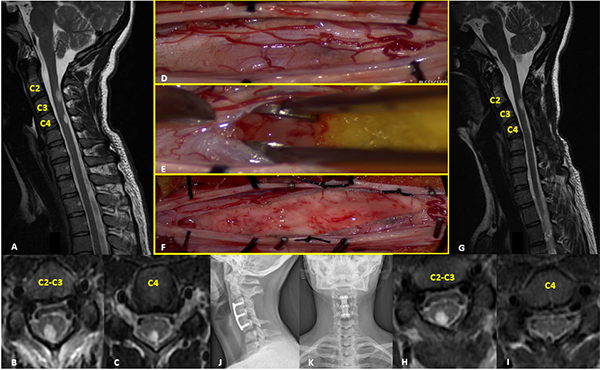

I: Ependimoma

Figura 1:

Ependimoma. A-D: RM prequirúrgica T1 con contraste y T2 cortes axiales y sagitales. E-F: Imágenes intraoperatoria pre y postresección. G-J: RM postquirúrgica T1 con contraste y T2 cortes axiales y sagitales.